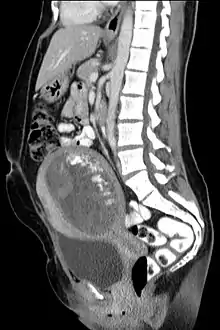

Hydatidiform mole on CT, sagittal view

Hydatidiform mole on CT, axial view

The diagnosis is strongly suggested by ultrasound (sonogram), but definitive diagnosis requires histopathological examination. On ultrasound, the mole resembles a bunch of grapes ("cluster of grapes" or "honeycombed uterus" or "snow-storm").[14] There is increased trophoblast proliferation and enlarging of the chorionic villi, and angiogenesis in the trophoblasts is impaired.[15]